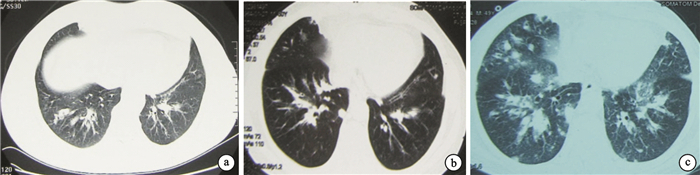

病歷摘要????患者男,49歲,因“咳嗽、氣促、間斷發熱、皮疹3個多月,加重1個月”入院。患者2013年12月初無明顯誘因出現咳嗽、咳白色泡沫樣痰,約100 mL/24 h,伴活動后氣促,低熱(約37.8℃),3 d后全身出現皮疹,以腹部和背部為主,瘙癢明顯。2014年1月12日至當地醫院就診,查血常規:白細胞計數16×109/L,嗜酸粒細胞6.85×109/L,支氣管舒張試驗陰性;胸部CT示雙肺散在斑片狀、結節影,雙下肺輕度支氣管擴張(圖 1a)。診斷為支氣管擴張,予頭孢哌酮舒巴坦鈉聯合左氧氟沙星抗感染治療。治療7 d,患者咳嗽、咳痰、氣促較前加重,體溫較前增高(達38.5℃),皮疹無明顯消退。2014年1月27日來我院門診,查血常規:白細胞計數17.97×109/L,嗜酸粒細胞11.21×109/L;胸部CT示雙肺病灶較前稍增多(圖 1b);纖維支氣管鏡示聲帶白斑病變,氣管下段、右中葉、右下葉內基底支、右背支有白色壞死物阻塞管腔(圖 2)。右中肺黏膜活檢示彌漫性混合性炎癥細胞浸潤,多為中性粒細胞。考慮支氣管肺炎、變應性血管炎,予以頭孢哌酮舒巴坦鈉、左氧氟沙星聯合抗感染,甲強龍40 mg Qd抗炎治療。治療5 d,癥狀無明顯好轉,查血常規:白細胞計數13.96×109/L,嗜酸粒細胞4.66×109/L,較前下降;胸部CT示雙肺斑片狀、結節影較前增多(圖 1c)。為求進一步診治于2月17日入院治療。起病以來,患者精神、食欲欠佳,睡眠差,因咳嗽、氣促難以入睡,大小便正常,體重無明顯變化。既往史:患者近7年反復出現雙上肢皮疹。對蝦過敏。

楊樹仁教授(放射科):患者多次肺部影像學檢查特點如下:雙肺多發支氣管柱狀、囊狀擴張,雙肺下葉部分支氣管壁稍增厚(可見于許多變態反應性疾病中);雙肺多發斑片狀、結節狀影,密度不均,邊緣模糊,病灶沿血管走形分布,隨著疾病發展,患者肺部病灶逐漸增多,雙肺門增大,縱隔內見多發腫大淋巴結;雙側胸膜未見異常。CSS患者的肺部表現無特異性,病變多樣,可表現為單側或雙側肺部游走性斑片狀、結節狀浸潤影或彌漫性肺間質病變,部分患者表現為支氣管壁增厚,支氣管擴張,部分患者伴有胸腔積液、胸膜增厚,有時有肺門、縱隔淋巴結腫大等,必要時可進一步完善肺血管成像幫助診斷。